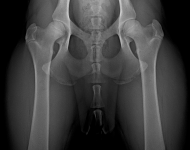

MVDr. Meloun: Lumbosakrální přechodový obratel